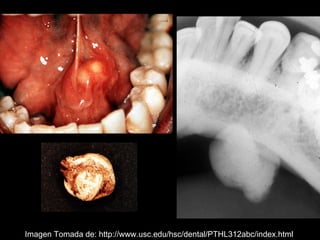

La sialolitiasis es la formación de obstrucciones mineralizadas en las glándulas salivales, causadas por el depósito de calcio y fósforo. Puede presentarse en las glándulas salivales mayores y menores, causando inflamación e hinchazón e incluso dolor durante las comidas. Los sialolitos se ven en radiografías como densidades radiopacas de varias formas y tamaños dentro de los conductos glandulares. El diagnóstico diferencial incluye otras imágenes radiopacas en los tejidos blandos.